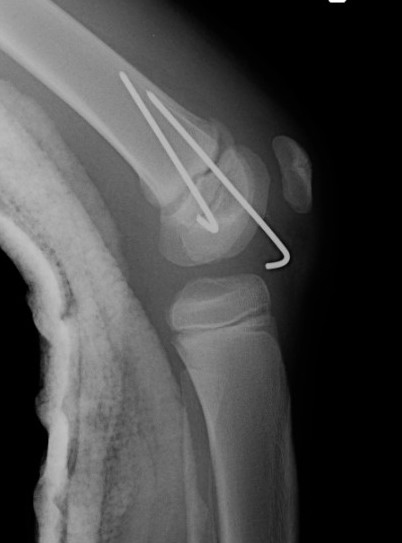

Distal Femoral Fracture SH2 APDistal Femoral Fracture SH2 Lateral

Salter Harris Type II

Distal Femur SH2 ORIFDistal Femur SH2 ORIFDistal Femur SH2 Lateral